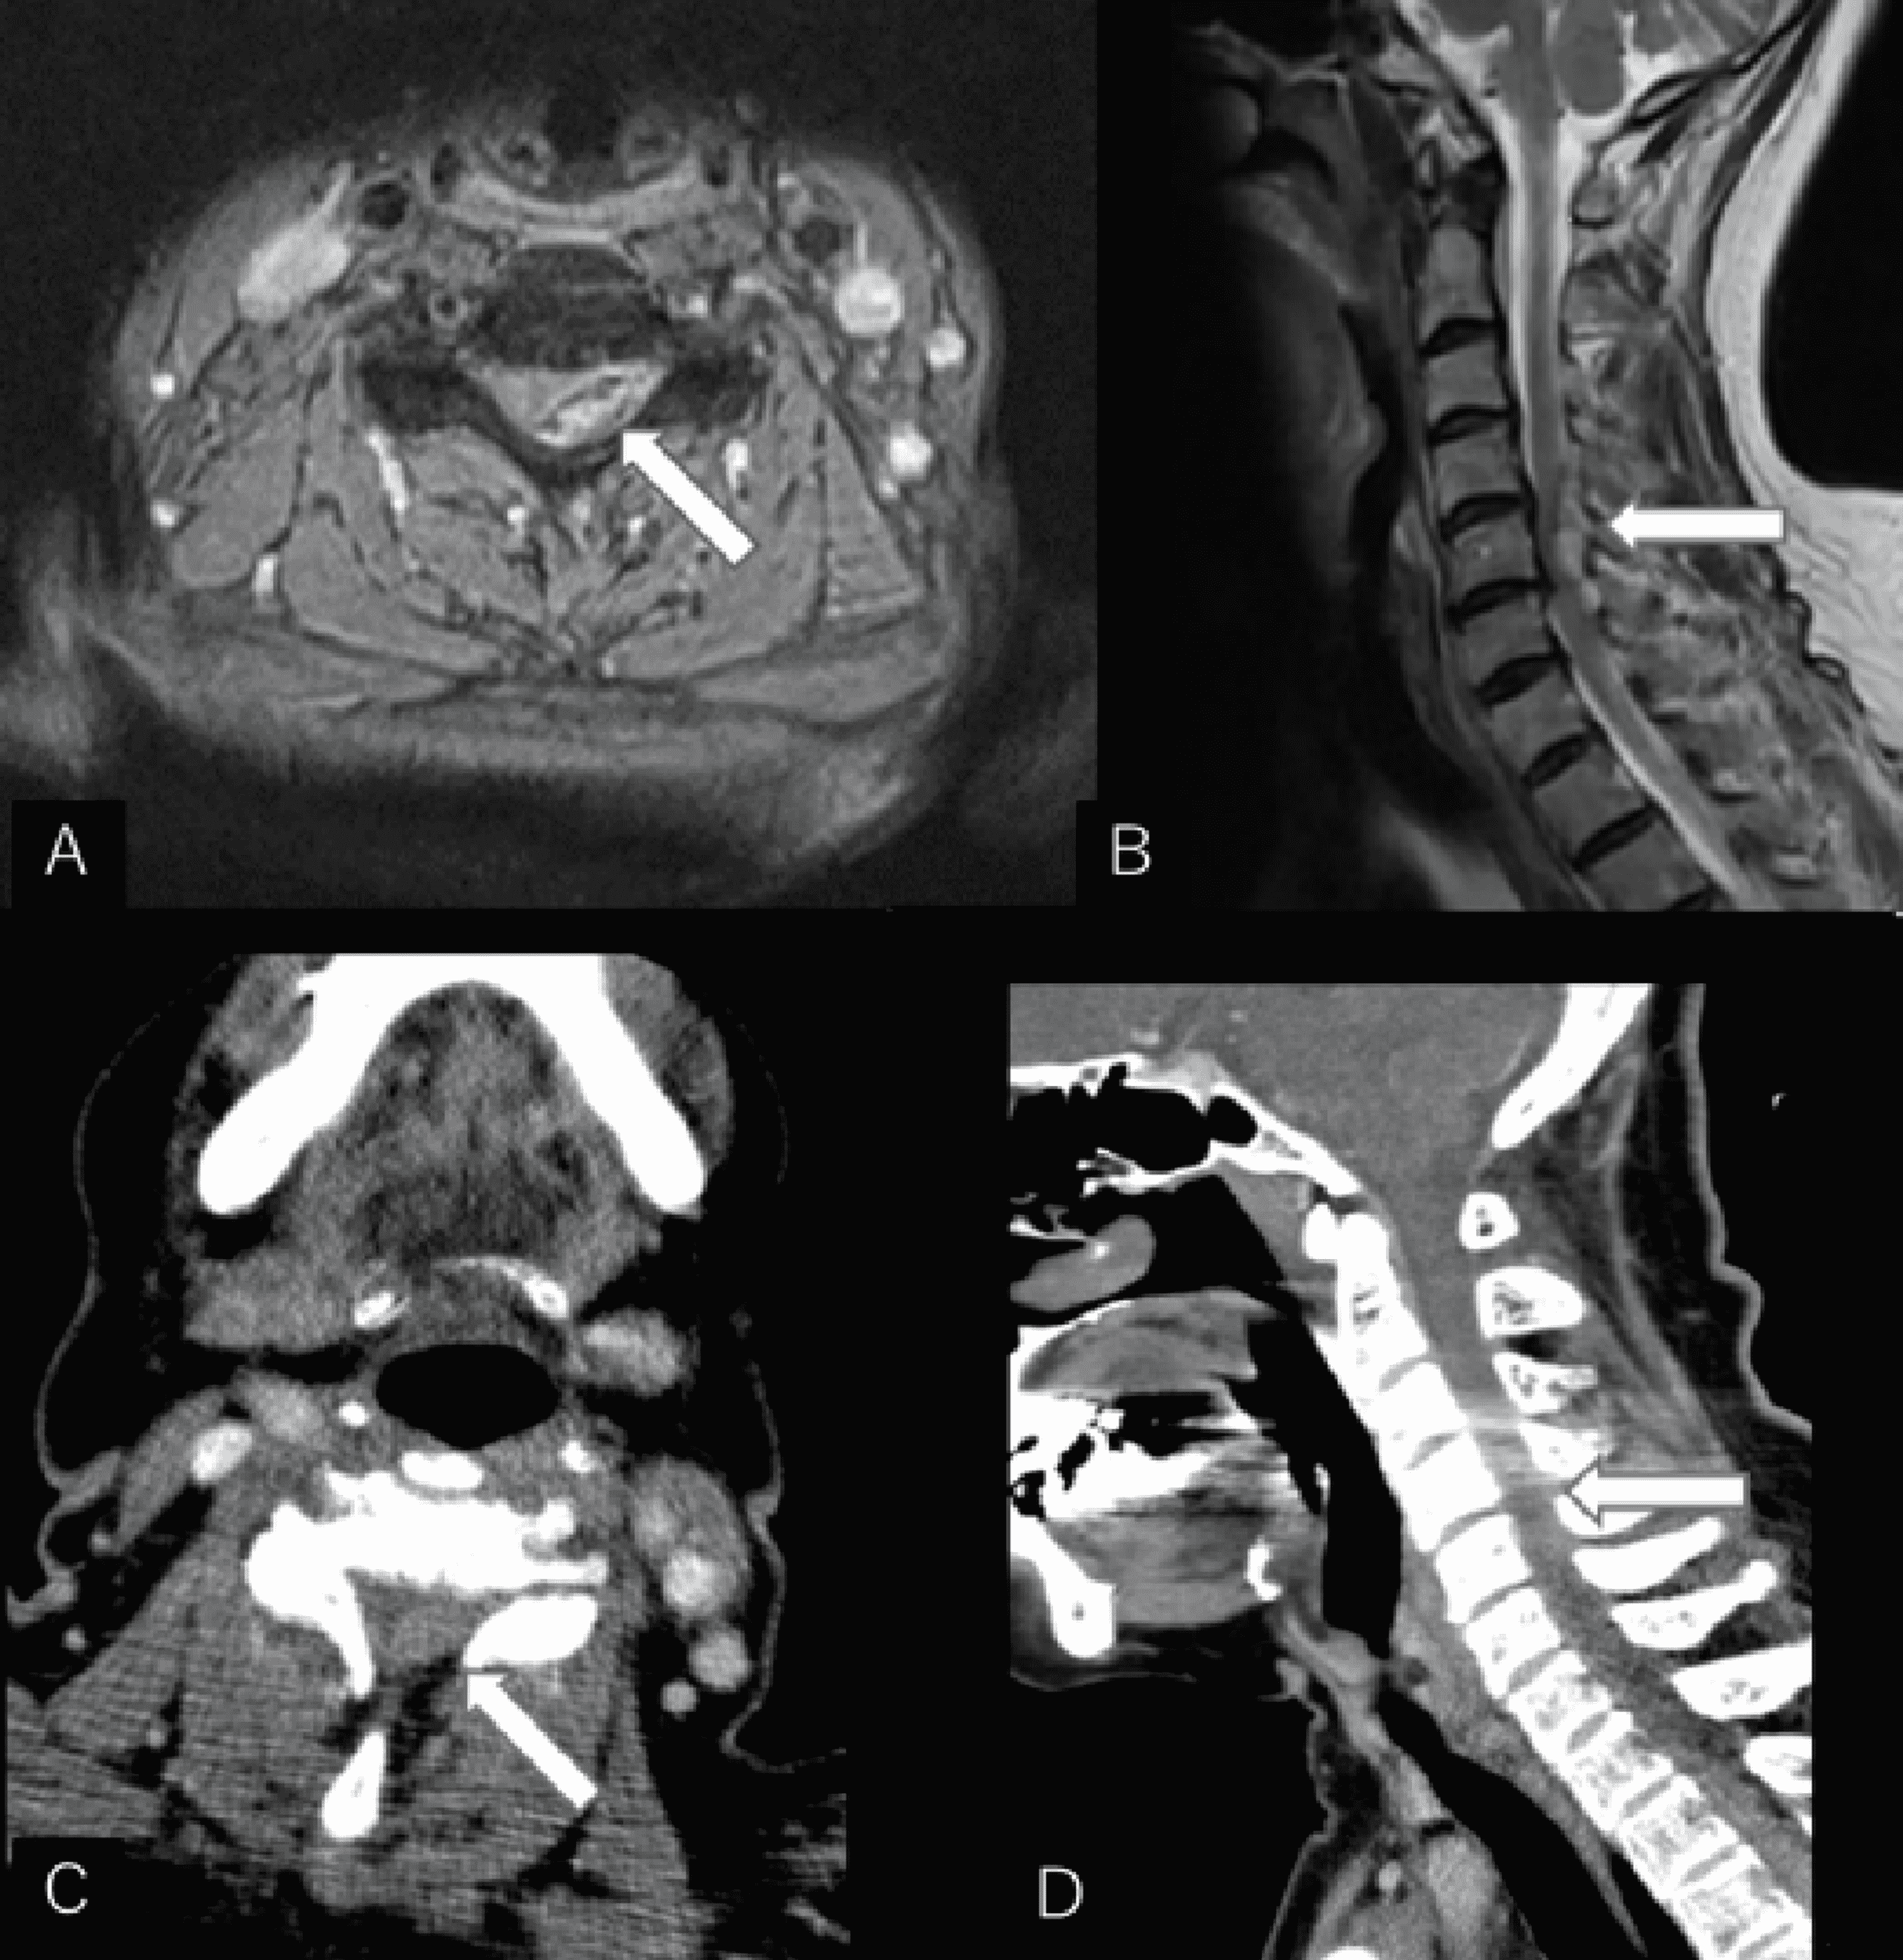

Imaging characteristics of the cervical epidural fistulas ( patient No

Imaging characteristics of the cervical epidural fistulas ( patient No Cervical Epidural Reddit My upper herniations are just one level below yours. cervical epidural steroid injection experience? The shot goes into a space near the spine. how do you diagnose it? epidural steroid injections in the cervical and thoracic spine can be used to treat cervical or thoracic herniated discs, radiculopathy,. a cervical epidural steroid injection is a shot. Cervical Epidural Reddit.